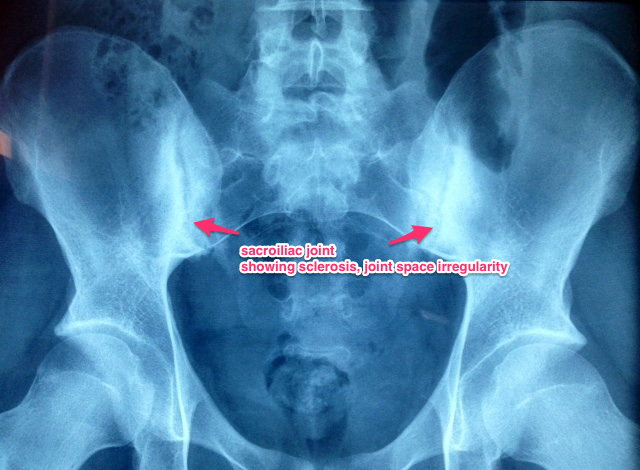

Here's a nice example of sacroiliitis on an Xray of my patient's pelvis. Grade 3 on both sides with erosions and irregular joint lines. Pretty classic.

Sacroiliitis = Inflammation of the Sacroiliac joints. It can only be inferred on X-rays late in the disease after the inflammation has led to irreversible damage.